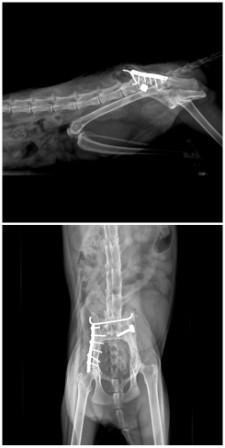

經醫師初步診斷腳有嚴重外傷,右邊腸骨骨折及左右兩邊腸薦關節脫臼,驗血結果為貧血及肝指數過高,可能是車禍撞擊造成出血及肝損傷動物近況說明: 現階段要等開刀部分的骨頭癒合~在以當下妹妹後腿萎縮情況有無改善或是惡化來評估是否進行電療.針灸之醫療.